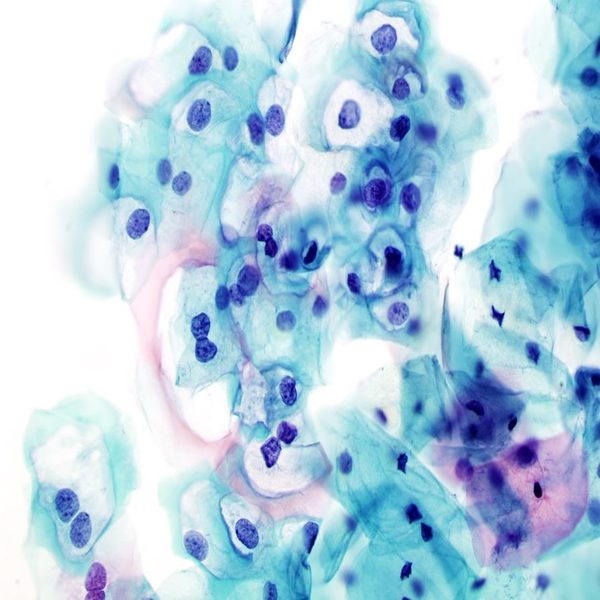

- General and specialized tissue and cell staining

- Immunocytochemistry (ICC) technique

Histological methods includes sample processing in the pathology laboratory, preparation of the slide and its examination under a microscope, sample fixation, molding, microtome cutting, staining and assembly of the slides.